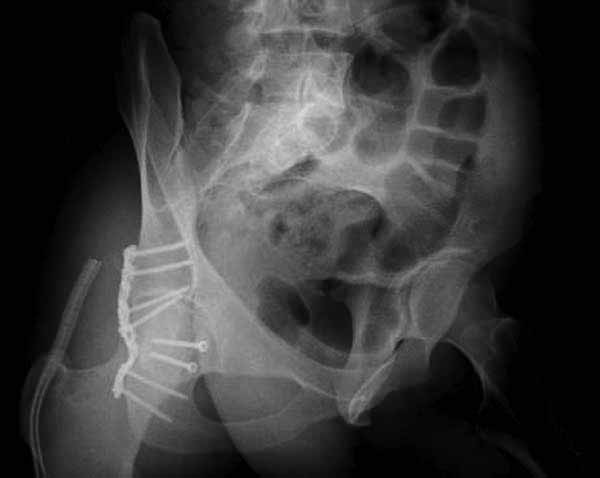

Представлены несколько вариантов фиксации: первый случай перелом головки с задним краем, операция из заднего доступа Кохер, а второй случай изолированный перелом головки - из трохантерного доступа.

Имя     : 5 Fem head  Postop.jpg

Тип     : image/jpg

Размер  : 25880 байтов

Описание: отсутствует

Url     : http://weborto.net:8080/pipermail/ortho/attachments/20111231/d311d17a/attachment-0019.jpg